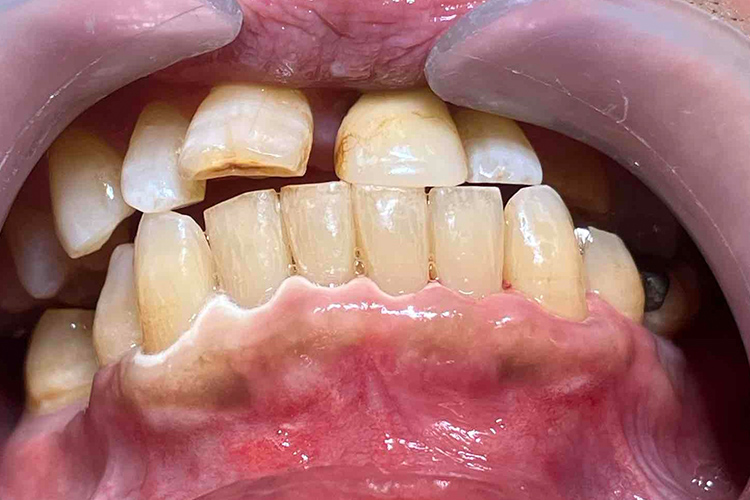

実際の実施例2

この患者様は、スケーリングより歯周ポケットが6mm以上ある患者様で患者様ご本人も歯周病になりかけている自覚がありました。また、口臭も気になされていましたので、ブルーラジカルの適用症例と判断し、施術を行いました。

(実施前)

施術前のレントゲンと口腔内写真です。施術前にプラークの除去を行ってから、施術します。